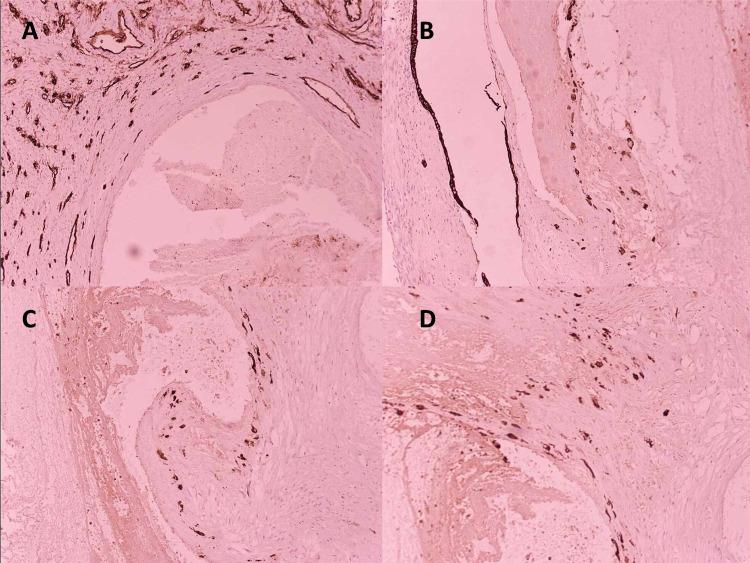

Subinvolution of the implantation site is a significant contributor to delayed postpartum hemorrhage (PPH). There is immense literature documenting the histologic features, development, and involution of the uteroplacental site; however, practice-oriented literature on subinvolution of the implantation site is sparse. In the present study, we briefly review the physiologic characteristics associated with the normal development and involution of uteroplacental arteries and the proposed pathophysiologic attributes of subinvolution. Furthermore, we engage in a comparison of the condition with preeclampsia. Herein, we report a case of postpartum vaginal bleeding that persisted for two weeks following cesarean delivery. The bleeding was nonresponsive to conservative treatment. Sonography performed revealed that a heterogeneous intrauterine vascular mass measuring 14.6 × 9.2 × 10.4 cmwas present, distending the uterine cavity. The presence of retained products of conception could not be ruled out. Therefore, to further confirm the condition, the patient underwent an emergency hysterectomy. Gross examination showed an enlarged and boggy uterus with numerous dilated and ecstatic thrombosed blood vessels in the implantation site of the endomyometrium. Histologic and immunohistochemical examination of the implantation site revealed the presence of persistently patent uteroplacental arteries with variable degrees of thrombosis adjacent to normally involuted vessels. Hence, a diagnosis of placental site vessel subinvolution (VSI) was established in this case. We also reviewed the related literature to illustrate the informative histologic findings of subinvolution. Preparing the ground for diagnosing subinvolution is important as this process defines that the cause of delayed postpartum uterine bleeding is idiopathic, rather than iatrogenic.

着床部位复旧不全是导致产后出血延迟的重要原因。有大量文献记录了子宫胎盘部位的组织学特征、发育及复旧过程;然而,关于着床部位复旧不全的实用性文献却很稀少。在本研究中,我们简要回顾了与子宫胎盘动脉正常发育和复旧相关的生理特征以及复旧不全的病理生理特征。此外,我们还将这种情况与子痫前期进行了比较。在此,我们报告一例剖宫产术后持续两周的产后阴道出血病例。保守治疗对此出血无效。超声检查显示宫腔内有一大小为14.6×9.2×10.4 cm的不均匀血管性肿物,使宫腔扩张。不能排除有妊娠物残留。因此,为进一步明确病情,患者接受了急诊子宫切除术。大体检查显示子宫增大、质地软,子宫内膜肌层着床部位有许多扩张、充血的血栓形成血管。对着床部位进行组织学和免疫组化检查发现,与正常复旧的血管相邻处存在持续开放的子宫胎盘动脉,并伴有不同程度的血栓形成。因此,本例诊断为胎盘部位血管复旧不全(VSI)。我们还回顾了相关文献以阐述复旧不全的重要组织学发现。为诊断复旧不全做好准备很重要,因为这一过程明确了产后子宫出血延迟的原因是特发性的,而非医源性的。